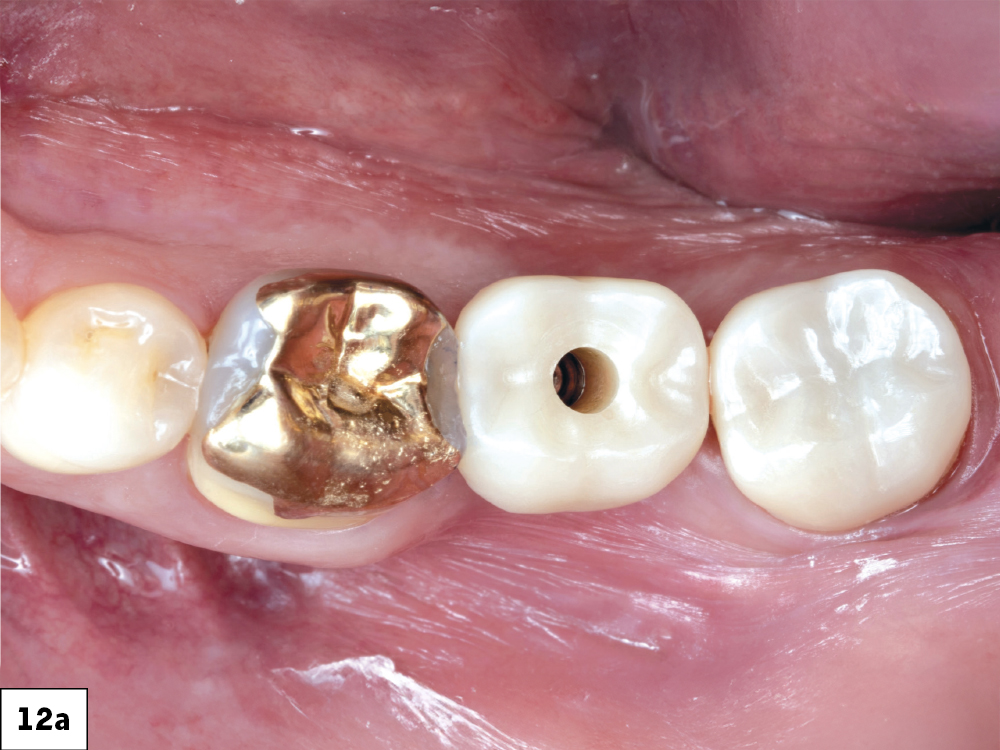

BruxZir NOW SRC in mouth with open access channel

BruxZir NOW SRC in mouth with closed access channel

BruxZir NOW SRC in mouth radiograph

Figures 12a–12c: The screw-retained crown was seated and the access channel sealed with Teflon tape and composite. The final restoration showed ideal contacts, occlusion and emergence profile.